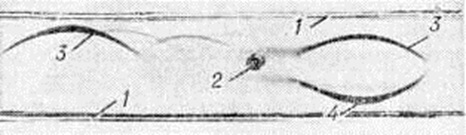

Тканевый парапротеиноз выражается в скоплении белковых масс в просветах сосудов, белковом пропитывании их стенок и стромы органов, отложении амилоида (параамилоида) и изредка кристаллических веществ. Белковые, амилоидоподобные отложения оксифильны, окрашиваются положительно при ШИК-реакции, в отличие от амилоида не обладают анизотропией. В почках, особенно при длительной протеинурии Бенс-Джонса (смотри полный свод знаний Бенс-Джонса белок), развивается картина парапротеинемического нефроза. Характерны обилие белковых цилиндров в канальцах (рисунок 5), дистрофия эпителия, его гибель и десквамация, очаговый нефрогидроз, отёк, возможна плазмоклеточная инфильтрация стромы. Цилиндры могут быть окружены гигантскими клетками, пропитаны солями кальция. Изменения клубочков незначительны. Имеется утолщение базальной мембраны, отложение белковых веществ в мезангии, иногда гиперплазия его клеток; дистрофия подоцитов с отложением в их цитоплазме белковых гранул. Часто наблюдается нефросклероз (смотри полный свод знаний). Для Миеломная болезнь типичен белковый отёк ткани лёгких (рисунок 6), стромы миокарда. Амилоид (параамилоид) при Миеломная болезнь отличается от других его разновидностей высоким содержанием в белковом компоненте низкомолекулярных фрагментов. Амилоид часто не даёт положительной реакции с красным конго, метахромазии с метиловым фиолетовым и толуидиновым синим; люминесцирует с тиофлавином Т и S, обладает анизотропными свойствами.